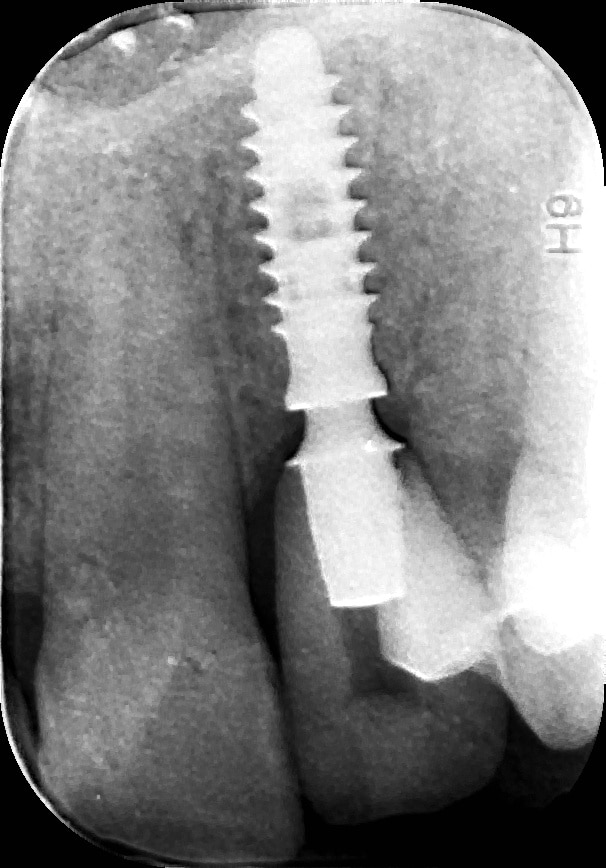

rx follow up 18 month post loading

La pz N.G. di anni 52 (ASA 1) viene visitata nel mese di settembre 2017 per la mobilità ed inestetismo dell’elemento protesico 22, (foto iniziali sequenza 1) si evidenzia una frattura parziale della radice, si decide per l’estrazione ( foto sequenza 2) e sostituzione dell’elemento con un restauro implanto-protesico. Purtroppo la scarsa quota ossea apicale all’alveolo post-estrattivo (foto 2 rx) e l’alta valenza estetica dell’elemento ci rende cauti e si programma una socket preservation post estrattiva con l’ausilio delle membrane di prf (foto prf e socket sequenza 3 e 4). Durente i 5 mesi di guarigione la pz porta una protesi parziale mobile (foto 5,2) , a guarigione del sito post estrattivo si evidenzia una buona conservazione dei volumi osseo-gengivali,(foto guarigione sequenza 6) se pur presente una recessione distale all’elemnto 21.Nel mese di febbraio 2018 si procede all’inserimento di un impianto max-stability 3,75x12mm disegnando un lembo anticipato palatino per consentire un aumento dei tessuti vestibolari suturando con tecnica rool flap e trasformando l’elemento parziale mobile in una corona singola a carico immediato sul moncone temporameo applicando i concetti protesici bopt , (foto impianto moncone protesi provvisoria sequenza foto 7-8-9). Durante il periodo di maturazione dei tessuti molli vengono apportate opportune modifiche ai profili del provvisorio al fine di dare maggior spazio al tessuto gengivale, ( fotosequenza 10).Dopo circa 2 mesi dal protesizzazione provvisoria si è proceduto alla realizzazione del manufatto protesico con tecnica chair side sirona con l’ausilio del t-base (foto sequenza 11-12-13), realizzando in una sola seduta una corona in disilicato, ottenendo un risultato più che soddisfacente (Foto 14). Nel controllo a 3 mesi dal carico definitivo si apprezza la perfetta conservazione dei livelli ossei e gengivali. (foto sequenza 15).concludo con un follow up a 18 . Tengo a sottolineare che un caso come questo è stato conducibile con buoni risultati solo grazie alla piena fiducia della pz e alla sua massima motivazione e collaborazione. Ad oggi la pz sorride soddisfatta del risultato. E questo rappresenta la massima ricompensa di chi dedica tutto se stesso alla professione.